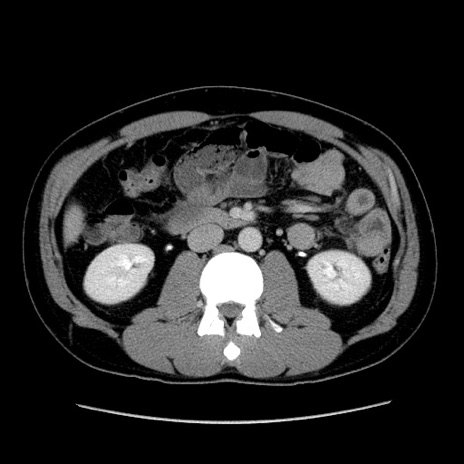

症例4(横断像)

【症例】30歳代男性

【主訴】腹痛、嘔吐

【現病歴】昨晩から突然の腹痛あり、その後嘔吐、軟便も出現。腹痛が改善しないため救急搬送となる。2日前にしめ鯖の食事歴あり。

【身体所見】意識清明、苦悶様、BP 135/90mmHg、BT 35.7℃、腹部:平坦、やや硬、心窩部〜臍部に自発痛、圧痛あり、筋性防御+、反跳痛-

【データ】WBC 8100、CRP 0.57